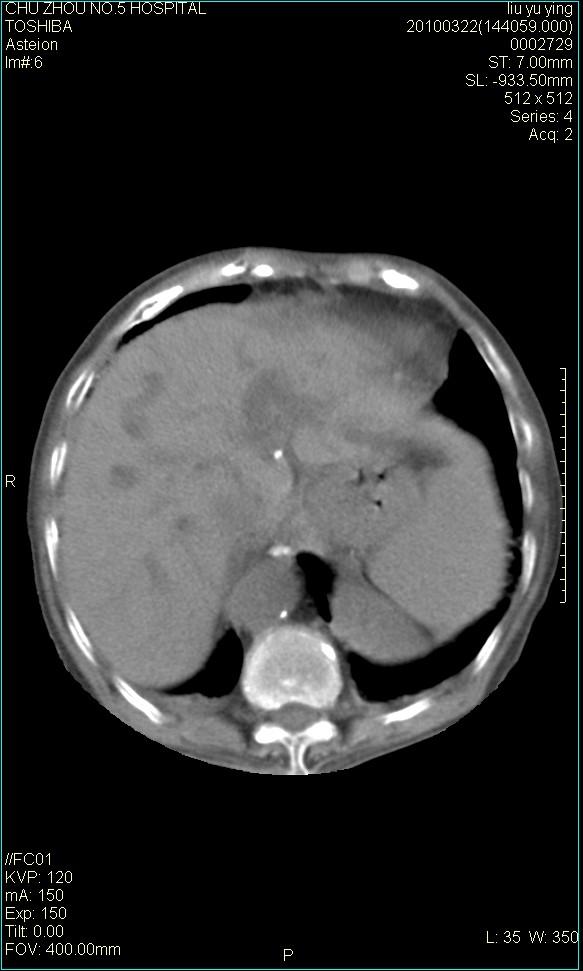

以下是引用科室第一人在2010-3-23 6:50:00的发言:[br]胆总管下段梗阻,多为肿瘤性病变,巨形胆囊,胆囊炎胆囊窝积液。[br]双侧胸腔积液,右降

以下是引用随光逐影在2010-3-23 8:12:00的发言:[br]1)胆系低位梗阻(肝内外胆管扩张,胆囊增大),原因待查。2)胆囊炎。3)双侧少量胸腔积液。4)降主动脉迂曲。